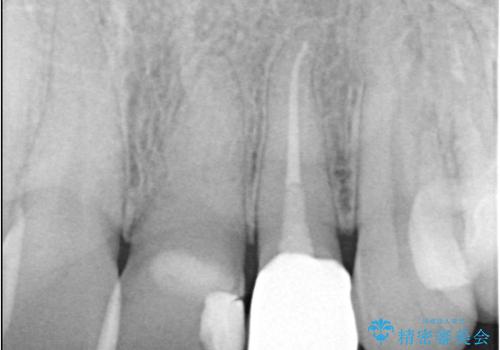

左上2番の唇側歯頚部が欠けており、根管治療を受けている歯でした。

レントゲン写真撮影を行ったところ、歯の中の土台が外れ欠けている状態でしたので土台と被せものの治療を行うこととしました。

外れ欠けている土台をまずやり替えた後、根管治療後の緊密な封鎖を目的としオールセラミッククラウンをセットしました。